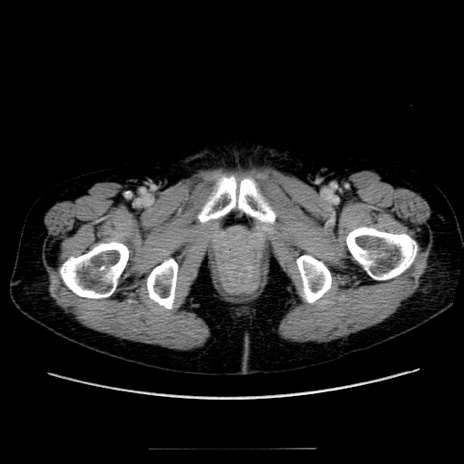

症例5(横断像)

【症例】70歳代女性

【主訴】お腹が張る

【現病歴】1週間くらい前から腹部膨満の自覚あり。昨日夜から増悪したため、本日救急外来受診。

【身体所見】意識清明、BT 36.5℃、BP 165/106mmHg、HR 80bpm、SpO2 98%、腹部:膨満、軟、自発痛・圧痛なし、触診にて不快感あり、腸蠕動音:減弱

【データ】WBC 12600、CRP 1.04